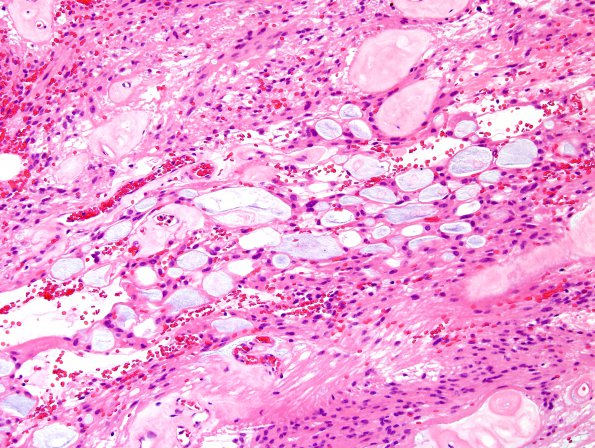

Washington University Experience | NEOPLASMS (GLIAL) | Ependymoma, myxopapillary | 3B3 Ependymoma, myxopapillary (Case 3) H&E 3.jpg

H&E stained sections show multiple fragments of a well-circumscribed, partially encapsulated, ependymal neoplasm. There are some areas of bland infarct-type necrosis. There are patchy areas of microcysts that contain extracellular pale basophilic material. There are abundant thickened and hyalinized vessels.